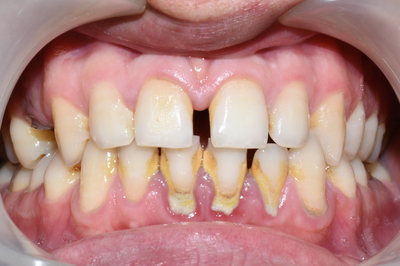

아래는 저희 치과에서 스켈링을 받으신

20대 환자의 사진입니다. [환자분의 동의를 얻은 사진만 포스팅합니다]

스케일링 전후사진이 있어 치석사진이 있으니 보고 싶지 않으신 분들은 주의해주세요.

치석이 아주 많이 쌓인 모습. 잇몸도 부어있습니다.

20대초의 나이임에도 불구하고 구강관리가 잘 되지않고 치석이 많이 쌓인 모습, 잇몸도 전반적으로 붉은 모습을 볼 수 있습니다.